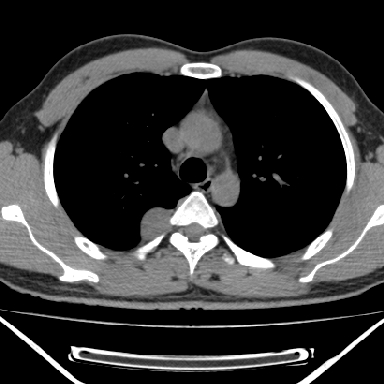

右上后纵隔脊柱旁类圆形肿块,边界光整,与胸腔呈钝角,首先考虑来源于肺外,神经源性肿瘤(神经鞘瘤可能大,神经鞘瘤)

病灶与椎间孔间存在脂间隙,病灶较大,椎间无明显异常改变,与胸膜移行处可见尾状影,考虑胸膜肿瘤,以良性间皮瘤可能性大

右上后纵隔脊柱旁类圆形肿块,边界光整,与胸腔呈钝角,首先考虑来源于纵膈,神经源性肿瘤可能大。

右上后纵隔脊柱旁见长椭圆形肿块,边界光整,与胸壁呈钝角。周围骨质未见异常。

考虑、1、后纵隔神经源性肿瘤;

2、不除外单发胸膜间皮瘤。